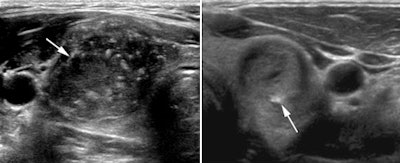

| Left, malignant hypoechoic solid nodule with central areas of calcification and an STSI of 20.1. Right, benign hypoechoic nodule with peripheral calcifications and an index value of 5.6. Images courtesy of the Journal of Ultrasound in Medicine. |

At 18.43 ± 5.99, the mean STSI for the 12 malignant nodules was significantly higher than the mean index of 6.82 ± 3.54 for the 39 benign nodules (p = 0.00002). The area under the ROC curve for diagnosing papillary carcinoma was 0.942 for distinguishing between malignant and benign nodules.

From the ROC analysis, the researchers found that a cutoff index value of 10 yielded 100% sensitivity, 79.5% specificity, 60% positive predictive value, and 100% negative predictive value.